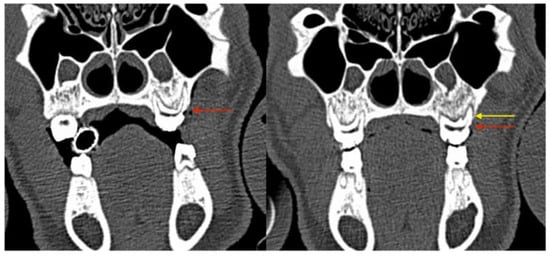

3.2.1. Clinical Evaluation

3.2.3. Radiological Evaluation